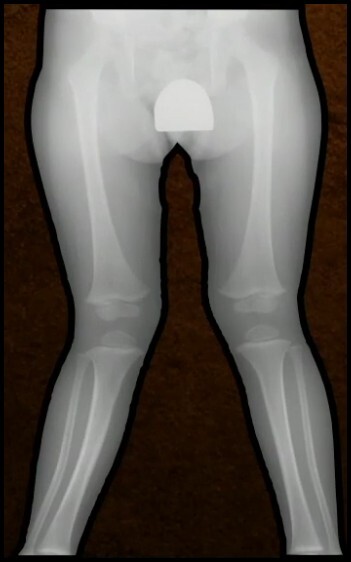

13

Q

FX Diafisária do Fêmur

Complicações (2)

A

Assimetria MMII

1. Encurtamento

2. Alongamento (SOBRECRESCIMENTO)

* ↓ 10 anos

* Masculino

* Proximal, cominuta ou obliqua